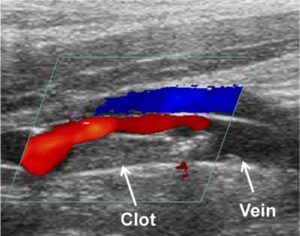

Addio ai vecchi manicotti per misurare la pressione. Grazie a una tecnica messa a punto in Olanda sara’ possibile usare gli ultrasuoni, con una procedura del tutto simile all’ecografia che permettera’ di avere dati su tutti i vasi sanguigni piu’ importanti.

Un’elaborazione matematica risale dall’immagine al valore della pressione, che in determinati punti e’ indicativa dello stato di salute dei vasi sanguigni, oltre che della persona in generale come le misure ‘tradizionali’. Il metodo e’ stato sperimentato sui maiali, e ora sono in corso test su alcuni volontari: “Con questo scan si possono trovare precocemente problemi vascolari – spiegano gli autori dell’universita’ di Eindhoven – e iniziare prima i trattamenti”.